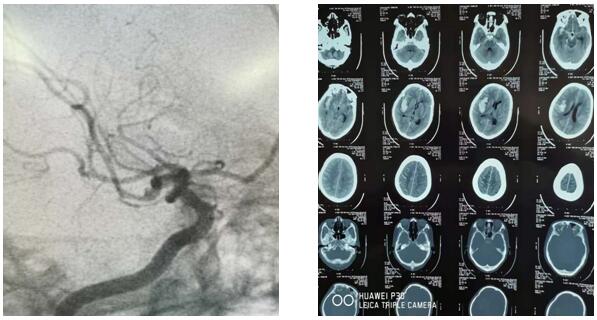

2019年6月7日10時30分,延安大學咸陽醫院神經外科二病區收治了一顱腦動脈瘤破裂出血患者,入院時頭顱CT示右側顳葉腦出血,量約30ml,破入蛛網膜下腔,由于出血部位及形態與常見的高血壓腦出血不同,主管醫師王海波考慮動脈瘤出血可能性大,建議行腦血管造影檢查,發現患者顱腦右側大腦中動脈下干近端血泡樣動脈瘤。瘤體大小為1mm*2mm,經科主任劉小雷、責任總醫師游文良及全科醫師討論后,判定出血原因為“血泡樣”動脈瘤破裂。手術組最終決定在顯微鏡下施行外科動脈瘤夾閉手術,同時清除血腫。由于“血泡樣”動脈瘤術中發生破裂大出血可能性較大,手術風險也隨之加大。相對血管內介入治療,此類手術為高難度、高風險的手術。需要更加扎實的血管解剖、顱底解剖知識和嫻熟的手術技巧。因此動脈瘤夾閉手術也被神經外科醫師們譽為“刀尖上的舞蹈”。 而這次的舞蹈是在最容易破裂大出血的“血泡”上表演。

此時患者已經陷入深昏迷,情況緊急,時間就是生命,已經沒有再多的時間考慮了,科主任劉小雷、責任總醫師游文良再次組織全科醫師討論,詳細向家人告知目前情況,最終決定急診開顱手術。如何避免術中發生大出血,成為擺在神經外科二病區團隊面前的最大問題。劉小雷主任,游文良責任總醫師帶領的神經外科團隊經過慎重、反復討論,決定由翼點入路夾閉動脈瘤并清除血腫。手術在全麻下進行。首先要通過腦自然間隙找到大腦中動脈下干,仔細分離,暴露動脈瘤,予以夾閉。整個過程都必須經過腦自然間隙進入顱腦深部,保證腦組織、血管和神經的完好,最后清除血腫,血腫腔嚴密止血。手術圓滿完成。目前患者處于恢復期,患者神志清,言語流利,思維清楚,除左側肢體肌力稍減弱外,其他功能均正常,在家人攙扶下可以慢慢行走。